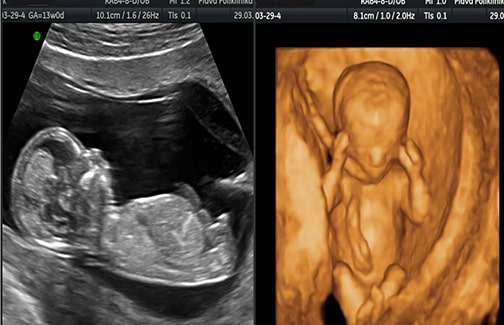

Ultrazvučni nalazi između 11. i 14. nedelje trudnoće: nuhalni nabor (mjerenje tekućine u području vrata ploda – svaki plod ima nešto tekućeg sadržaja, ali on je kod ploda s Downovim sindromom obično povećan), duzina nosnih kostiju, Dopplerski protok u ductusu venosusu, trikuspidalna regurgitacija.

S obzirom da takav pregled može raditi samo kvalificirani ljekar iskusan u tom području, koristeći ultrazvučni aparat visoke rezolucije, ljekari u našoj poliklinici posjeduju posebnu licencu Fetal Medicine Foundation (Svjetska institucija za fetalnu medicinu) za određivanje i analizu ultrazvučnih markera u ranoj trudnoći.

Svi pregledi se obavljaju u Plavoj poliklinici na trenutno najsavremenijem GE Voluson E8 expert ultrazvučnom aparatu. (u svijetu medicine!)